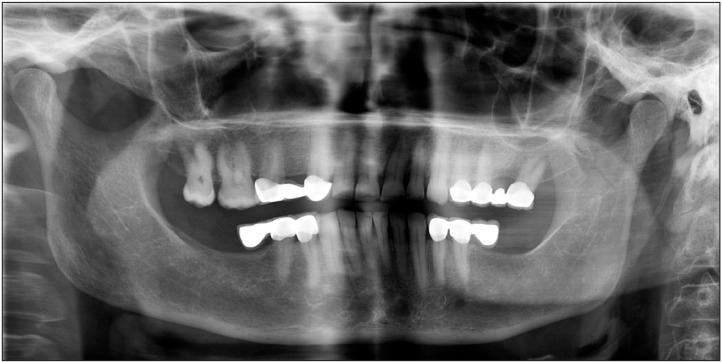

Leiomyoma is a type of benign smooth muscle neoplasm that is a common neoplasm of the uterus and gastrointestinal tract but rarely affects the head and neck region and is especially unlikely to affect the oral cavity. The diagnosis of leiomyoma is mainly determined by histopathological studies due to variation in its clinical appearance and symptoms. In the present paper we report two rare cases of gingival angioleiomyoma in the posterior maxilla and mandible. After total excision, hematoxylin-eosin and smooth muscle actin staining confirmed the diagnosis of angioleimyoma.